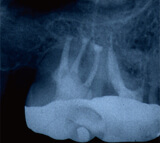

被せ物をした歯の違和感により来院されました

レントゲン写真により経過を確認します

黒い影は骨が溶け膿を持っている

黒い影が無くなり骨の再生が認められ経過は良好です